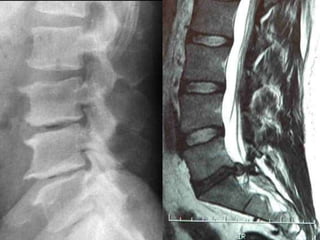

RX TC RMI

74% das RMI possuem anormalidade(s) sem dor!

(Jensen et al., 1994)